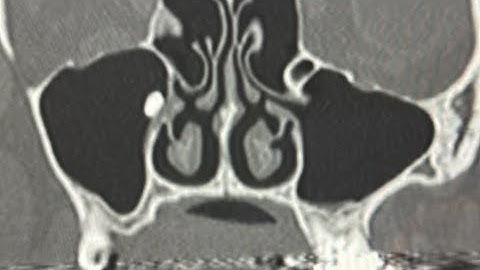

HOW to RETRIEVE a ROOT IN THE MAXILLARY SINUS! DISPLACED ROOT RETRIEVAL TUTORIAL